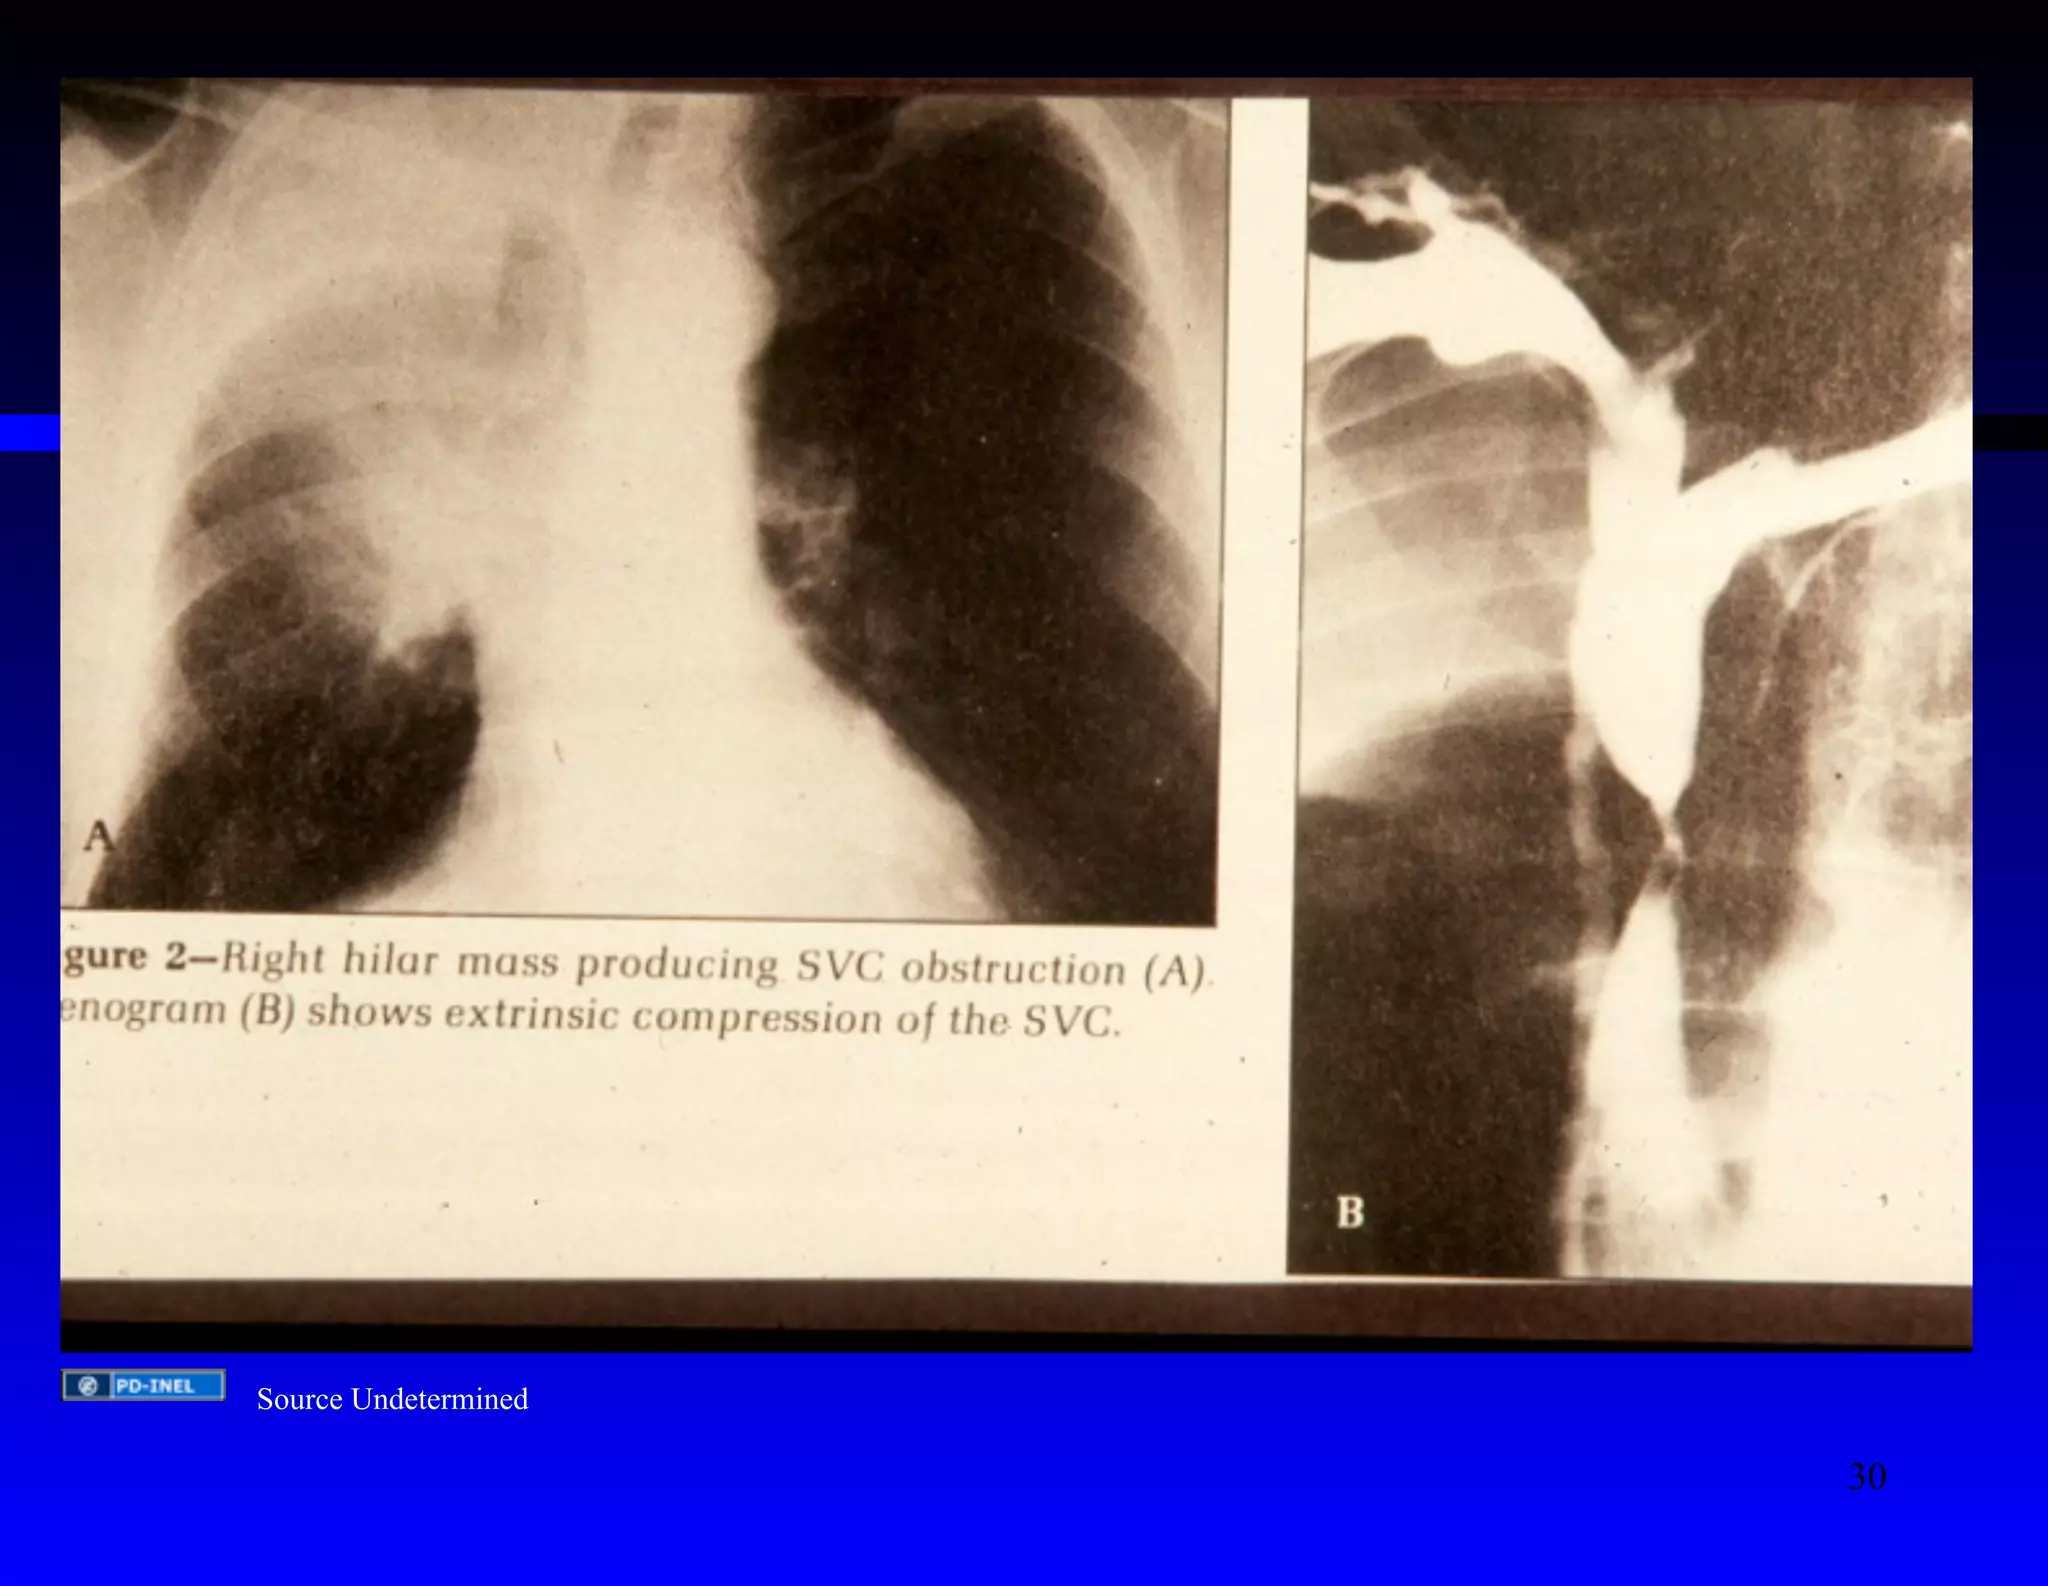

Source Undetermined

30